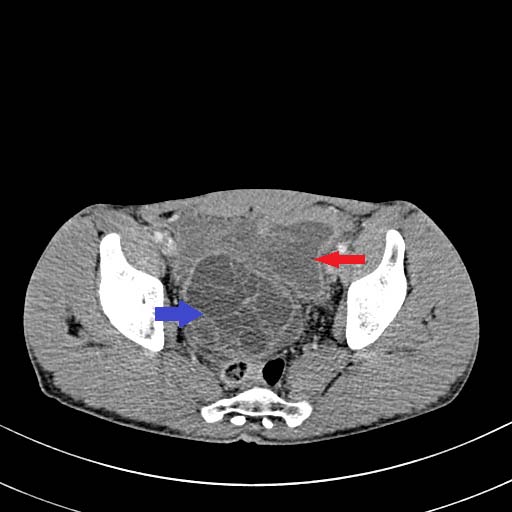

In this study 2 patients of sickle cell disease showed multiple bone infarcts involving iliac bones in addition to the AVN of femoral head. The most common quadrant involved in our study is anterosuperior quadrant seen in 62% of the heads followed by superior quadrant in 27 % cases.

Gabriel et al (5), in their study showed that involvement of anterosuperior quadrant is specific for AVN. Nishii et al (3), in their study showed that location and size of the lesion are the prognostic indicators of collapse and large necrotic lesions have likelihood to involve anterosuperior quadrant.

In this study most common MRI finding of AVN is double line sign seen in 99 femoral heads (85%) which is considered pathognomic of AVN.

Other common findings are contour loss(62%), joint effusion (70%), bone marrow edema(50%), joint space reduction(18%).